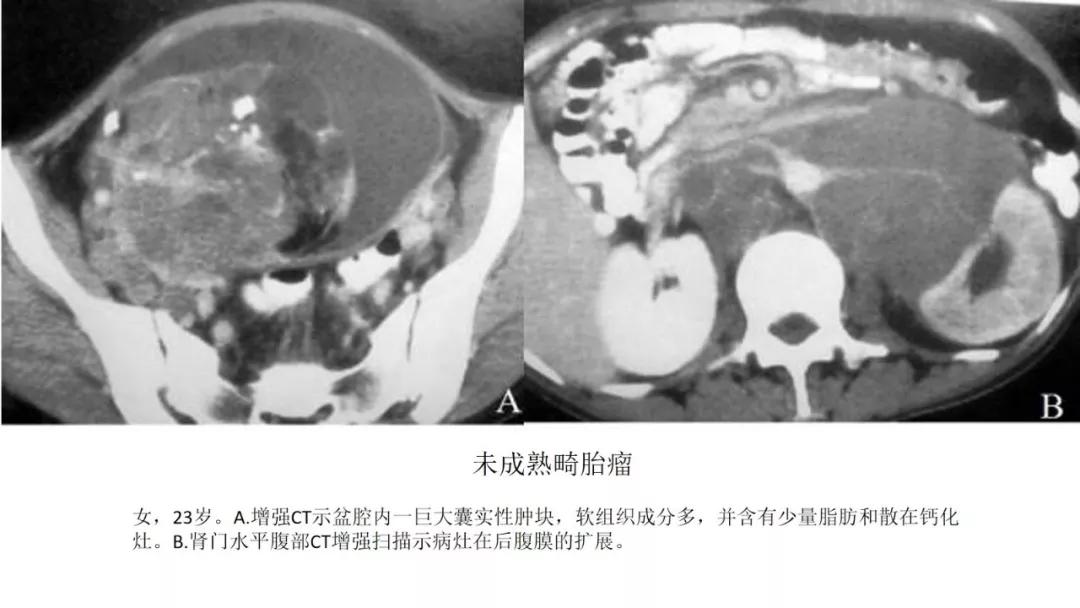

恶性者常呈实性或混杂性肿块,多数边界清楚,可伴有不规则沙粒状钙化。无性细胞瘤常为实性肿块,轻度强化,内胚窦瘤实性成分明显强化,不成熟畸胎瘤呈混杂密度。结合年龄及临床生化检查,有助于诊断。